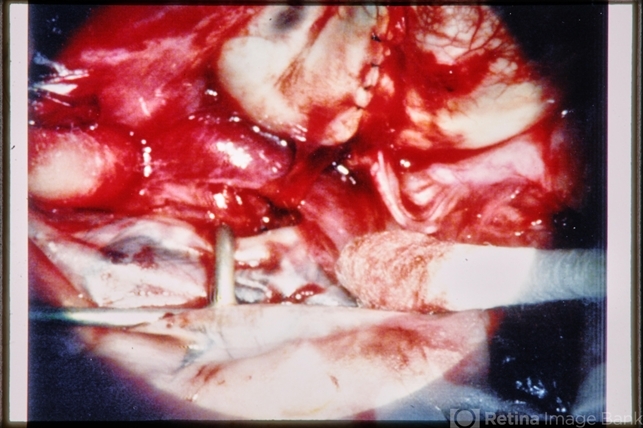

- trauma, scleral laceration

- Trauma – surgical view – long scleral laceration repair; probably hypotonous eye.